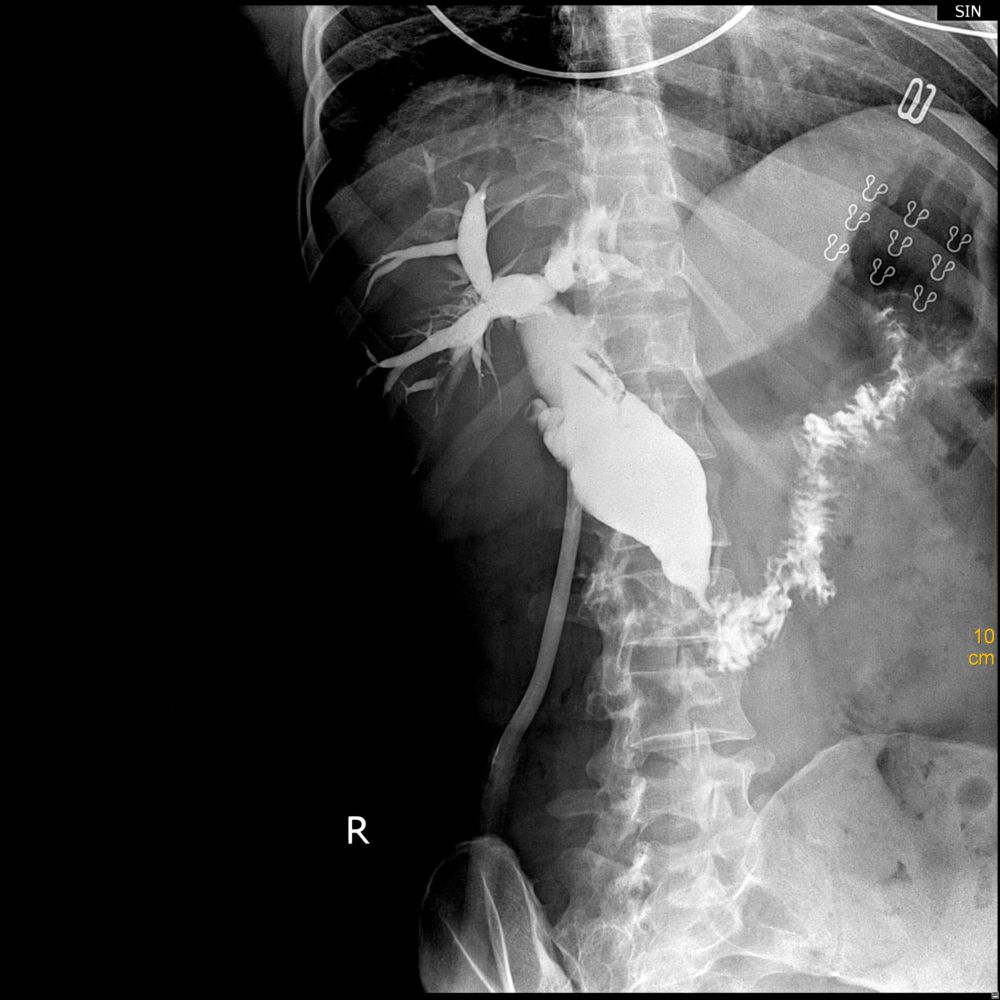

以下是引用luoxinjun在2010-10-2 14:11:00的发言:[br]1、肝内外胆管扩张明显,胆总管下端纤细,整体看呈萝卜根状改变,考虑胆总管下端炎症。[br]2、胆道长时间梗阻,胆道扩张,突然减压,胆道短时间不能回缩到正常状态,以至于造影检查时胆道扩张。

以下是引用ghp3522在2010-10-1 20:55:00的发言:[br]胆总管明显扩张,可疑胆总管末端结石狭窄。